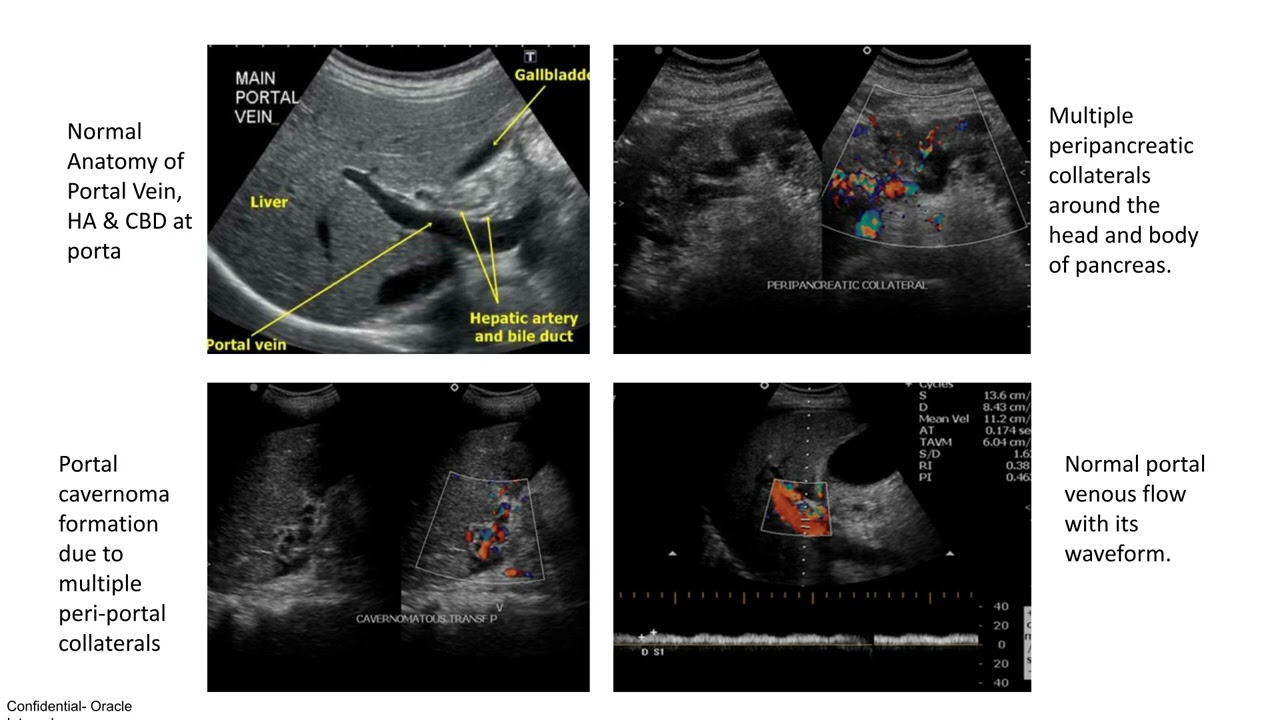

Шикха Кумари | УЗИ и цветная допплерография при портальной гипертензии